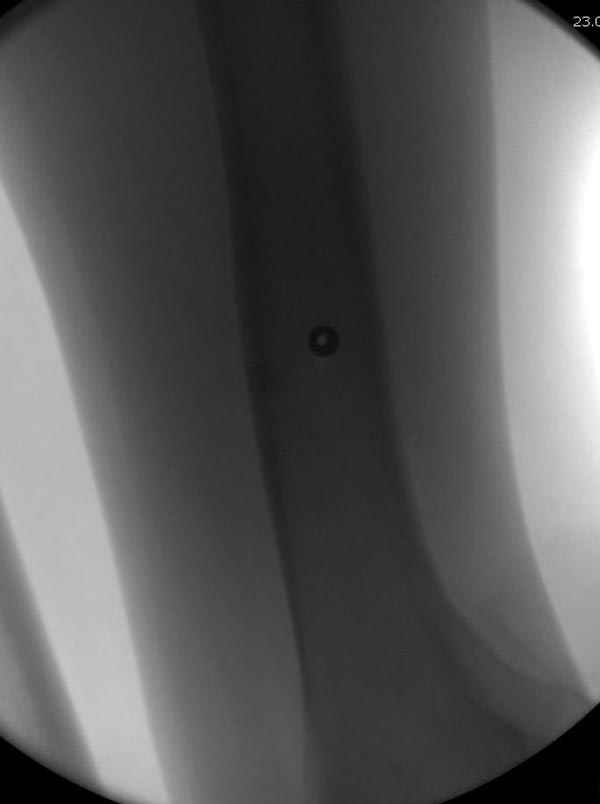

Учитывая, что больной получил травму не во время визита в церковь, и он является одним из представителем 40 миллионного “outstanding itizen”, без медицинской страховки, без работы в свои 39 лет, и без надлежающей ортопедической дисциплины у которого отсутсвует страх стрессового перелома, было рекомендовано оперативное лечение: профилактическое антеградное интрамедуллярное штифтование.

Методика штифтования при отсутствии большой зоны перелома как при онкологических профилактических штифтованиях, расверливание интрамедуллярного канала проводим с предварительным наложением дополнительного дренажного отверстия в дистальном отделе бедра (в данном случаи в канале оставили 6.5 мм канюлированный шуруп), иначе при создании давления в канале во время сверления имеется опасность эмболизации легочной артерии тромбом.